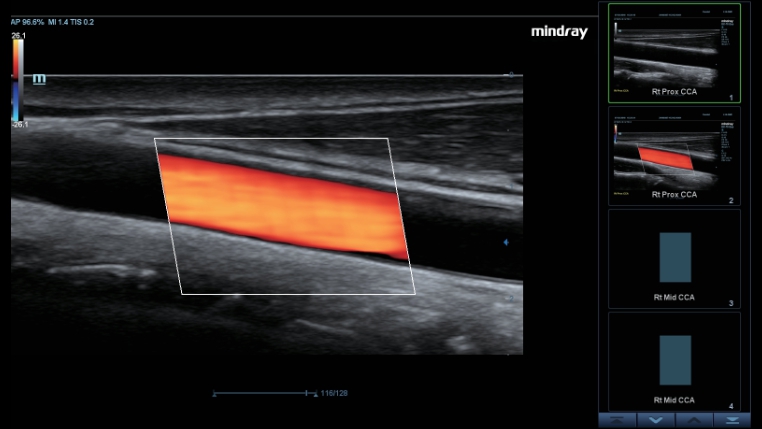

Smart Track

Funkcja Smart Track zapewnia szybk? i inteligentn? optymalizacj? obrazów naczyń krwiono?nych zaledwie po jednym klikni?ciu. Umo?liwia optymalizacj? w trybach Dopplera Kolorowego, Power Dopplera i Dopplera spektralnego PW poprzez samodzieln? detekcj? naczynia i skrócenie czasu niektórych etapów badania. W ten sposób cykl czynno?ci podczas badania naczyń krwiono?nych zosta? uproszczony z jednoczesnym zachowaniem optymalnego obrazowania.